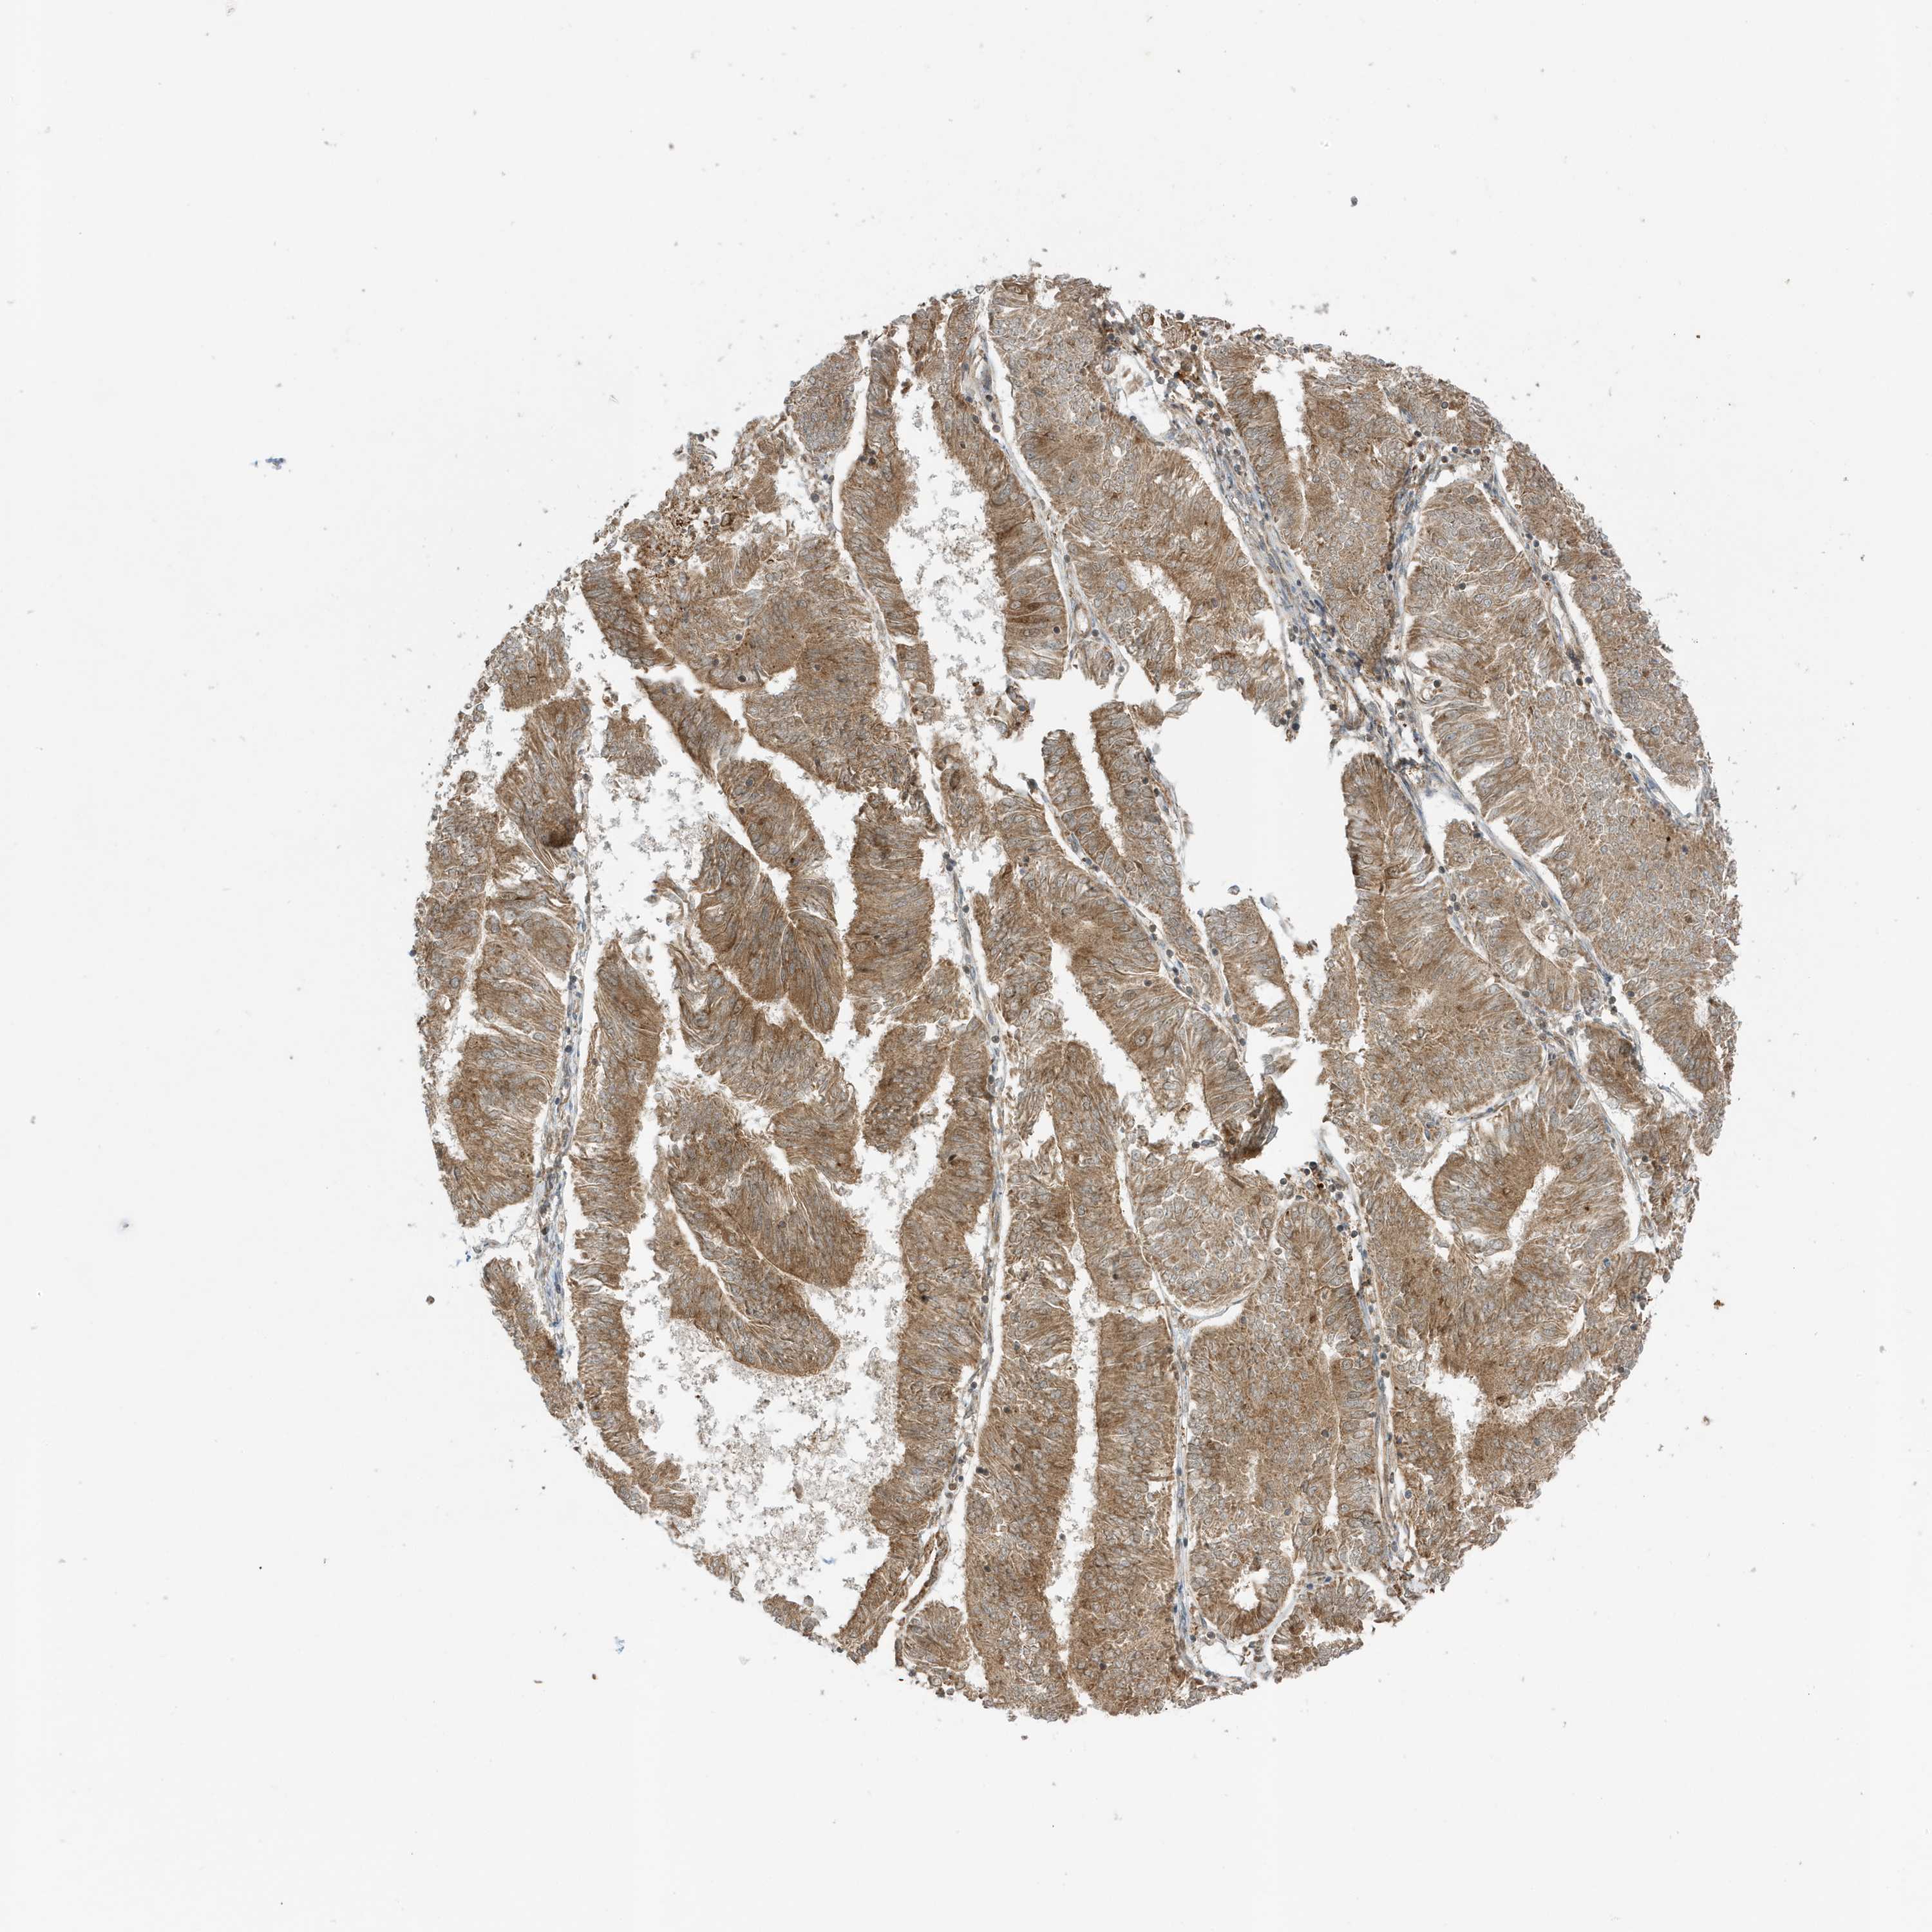

ENDOMETRIAL CANCER - Protein expressioni

A mouse-over function shows sample information and annotation data. Click on an image to view it in a full screen mode. Samples can be filtered based on level of antibody staining by selecting one or several of the following categories: high, medium, low and not detected. The assay and annotation is described here.

Note that samples used for immunohistochemistry by the Human Protein Atlas do not correspond to samples in the TCGA dataset.

Antibody stainingi

Antibody staining in the annotated cell types in the current human tissue is reported as not detected, low, medium, or high, based on conventional immunohistochemistry profiling in selected tissues. This score is based on the combination of the staining intensity and fraction of stained cells.

Each image is clickable and will lead to virtual microscopy that enables deeper exploration of all samples and also displays staining intensity scores, fraction scores and subcellular localization as well as patient and tissue information for each sample.

Antibody HPA035399

Staining

High

Medium

Low

Not detected

Intensity

Strong

Moderate

Weak

Negative

Quantity

>75%

75%-25%

<25%

None

Location

Nuclear

Cytoplasmic/membranous

Cytoplasmic/membranous,nuclear

Adenocarcinoma, NOS

Adenocarcinoma, metastatic, NOS